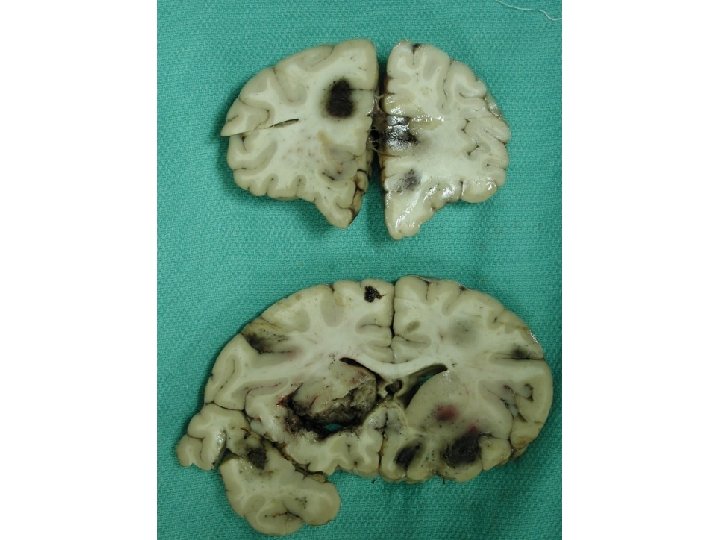

173 involved vessels 88 in grey matter, 85 in white matter Mean diameter 66. 7 ± 3. 9µm Mean ratio of wall thickness to diameter is 0. 18 ± 0. 01 Vessels < 100µm are venules/veins or arterioles/small arteries But ratio is ca. 0. 1 for venous vessels, ca. 0. 5 for arterial, so most are venous

Diagnosis • Acute vasculitis, mostly venous, in association with ulcerative colitis • Predominantly neutrophilic (acute) • Venous involvement explains the extensive hemorrhage since tissue is under arterial perfusion pressure